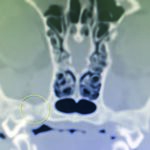

CT scan of skull is preferred for evaluate bone fractures and identify areas of acute hemorrhage or edema. CT scan showed multiple sites of skull fractures, right maxilla, both frontal, right zygomatic, right caudal mandible, right caudal zygomatic, right temporal, left occipital bone (Figure 3) and patchy small area of hyper-attenuation at the cranial of midbrain in pre-contrast study (Figure 4), no detectable mass effect, hypo-attenuated of large edematous parenchyma in the brain, right temporomandibular joint is displacement (Figure 5) and left tympanic bulla shows partial ventral fluid-filled.

Figures 4.1, 4.2

Patchy small area of hyper-attenuation at the cranial of midbrain in pre-contrast study.